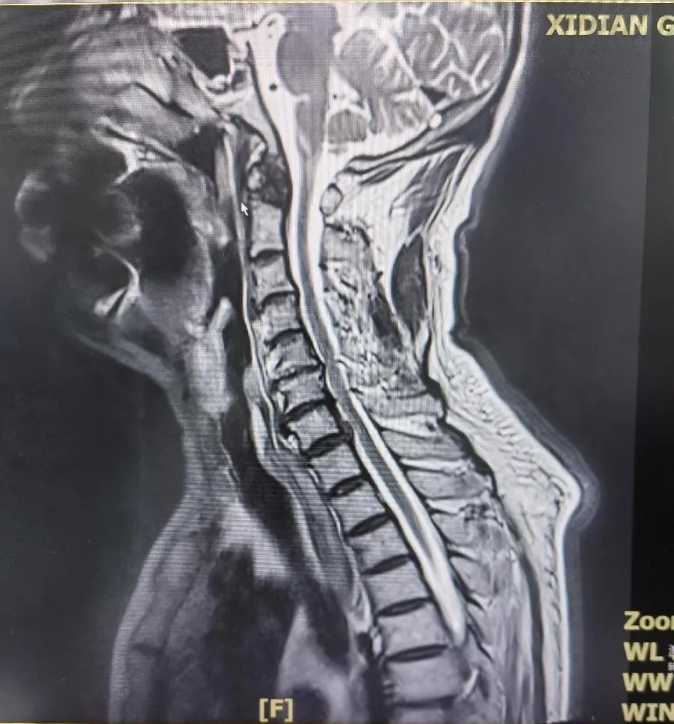

為了明確高大爺?shù)牟∏?,骨科張富軍主任團隊與神經(jīng)內(nèi)科姚力主任團隊密切合作,立即啟動了多學(xué)科會診機制。在完善各項檢查的基礎(chǔ)上,姚力主任親自對高大爺進行了詳細的查體,并安排電生理檢查進行輔助診斷。經(jīng)過細致分析和深入討論,專家團隊從臨床表現(xiàn)、影像學(xué)及電生理特征、鑒別診斷、臨床分型等多方面入手,對高大爺?shù)牟∏檫M行了全面評估。

最終,專家團隊排除了肌肉病變、脊髓型或神經(jīng)根型頸椎病、脊髓空洞癥及肌萎縮側(cè)索硬化癥等可能性,確診高大爺患有罕見的平山病。針對高大爺?shù)牟∏?,張富軍主任團隊為其制定了個性化的治療方案,并進行了詳細的健康指導(dǎo)。高大爺對醫(yī)院的診斷技術(shù)表示高度贊揚,并表示將積極配合治療。